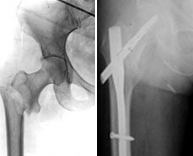

La pelvis articula con la porción superior del fémur dando lugar a la articulación de la cadera. Las fracturas de la cadera por afectación pélvica obedecen a traumatismos de alta energía como accidentes de tráfico y precipitaciones desde grandes alturas. Sin embargo, las fracturas de la porción superior del fémur, aunque también pueden producirse en pacientes jóvenes por los mecanismos anteriores, son fracturas más frecuentes en la edad avanzada y debido a mínimos traumatismos a causa de la osteoporosis a este nivel. El enorme espectro de fracturas que existe a este nivel es amplio y por tanto sus tratamientos distintos. Los tratamientos conservadores exigen grandes temporadas de encamamiento dada la localización de la lesión por lo que abogamos siempre que sea posible por cirugía mínimamente invasiva gracias a la cual con pequeñas incisiones se restaura con facilidad la anatomía devolviendo la articulación a su rango de movilidad habitual en el menor tiempo posible